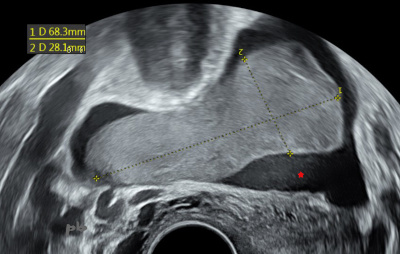

1-GEU gauche

- Volumineux caillot dans le cul-de-sac de Douglas, entouré d’un liquide hypoéchogène : hémopéritoine (★)